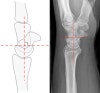

Scapholunate angle>60º, Radiolunate angle>15º를 보입니다.

* Scapholunate angle

Normal : 30 - 60°

Questionably abnormal : 60 - 80°

Abnormal : > 80° indicates instability of the wrist.

* Lunate axis

The axis of the lunate runs through the midpoints of the convex proximal and concave distal joint surfaces and can best be drawn by finding the perpendicular to a line joining the distal palmar and dorsal borders of the bone as demonstrated on the left.

Scapholunate angle<30º, Radiolunate angle<15º를 보입니다.